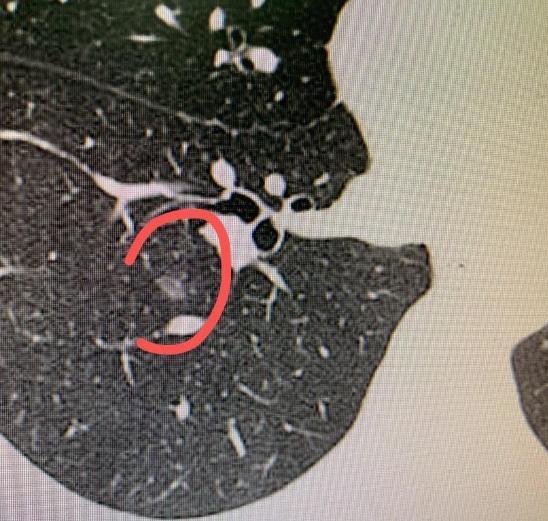

这位49岁的女患者,因为父母都曾患过癌症,所以一直很重视身体,每年坚持体检。就在最近,她在右肺发现了7个结节,其中最大的一个位于右下肺,直径1.3厘米,里面已经出现实性成分。 发现多发性肺结节,确实让人紧张。如果马上手术,创伤范围会比较大;但若一直不变,其实也是安全的。所以最初我是建议她定期复查,密切观察。 直到最近一次CT检查,发现其中1.3cm的结节密度增加了,这说明肿瘤在生长,不能再等了,必须手术处理。 既然决定手术,我们就面临一个问题:能不能一次手术就把所有结节都处理干净,同时尽量保护肺部功能? 经过详细的三维重建规划,我们最终设计了一个联合手术方案:楔形切除加肺段切除。这样既完整切除了全部7个结节,又最大程度保留了健康的肺组织。 术后病理结果也很有意思:这些结节性质并不相同,从不典型腺瘤增生、原位癌,到微浸润癌甚至浸润癌,各种类型都有。 这个病例也提醒我们,面对肺多发结节,不一定都要急着手术。多数情况下,规律随访是安全的;只有当结节出现变化时,才需要考虑手术干预。 很庆幸,这次手术非常顺利,患者肺部损伤很小,术后第二天就能下床活动了。一次手术,解除了多个隐患,也让她彻底放下了心里的负担。[玫瑰][作揖]胸外科乔贵宾医生MCN双量进阶计划 [心]附:线下免费义诊!11月21日(周五上午),在南方医科大学珠江医院 门诊大厅